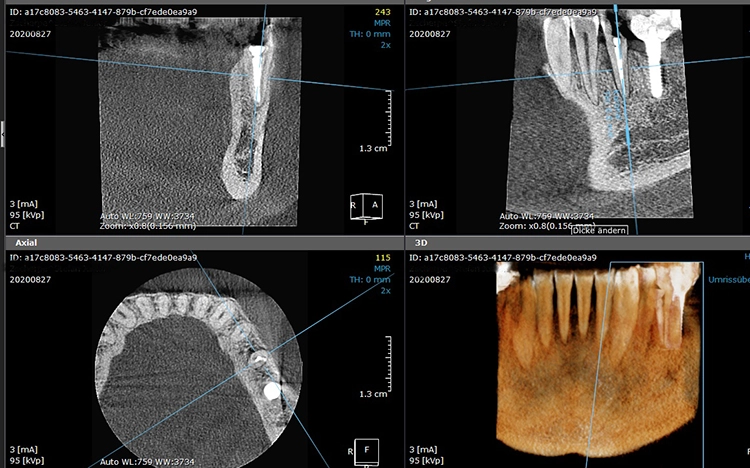

Bei diesem 49-jährigen, allgemeinanamnestisch unauffälligen Patienten liegen diverse ästhetisch störende Zahnstellungsanomalien vor, wobei Zahn 21 bei extremer Elongation frakturierte (Abb. 2a). Nach einer Übergangsversorgung mittels provisorischer Stiftkrone (Abb. 2b) entschied sich der Patient für eine Zahnentfernung bei gleichzeitiger Implantation. Im Ausgangs-DVT (Abb. 2c und d) zeigt sich im Cross-Sectional, wie weit der Processus alveolaris zurückliegt.